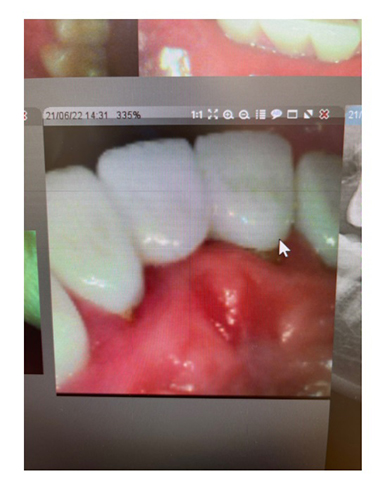

上下8本、全16本の歯を約500万円かけてジルコニアクラウンに入れ替えたアレンさん。6月上旬に食事をした際、「バキッ!」という音とともに鈍い痛みを感じ、前歯でかめない状態が数日間続いたといいます。

痛みが引いた後も違和感が続いたため、歯科でレントゲンを撮ってもらったところ、「ジルコニアは硬いから割れないかわりに、逆に土台の自分の根本の歯に衝撃が来て、中で土台の歯が割れる事がある」と、歯の土台が割れている可能性を告げられたとのこと。アレンさんは「ブリッジ自体が難しくなる上に、入れていたジルコニアも、支えがないから再度入れられない事になるし、土台となる根本がなかったら、もはやジルコニアすら被せられない」と、自身の歯が“笑えない事態”に陥ったことに大打撃を受けた様子でコメントしていました。

歯を巡る受難は終わらず、何軒かの医師を訪問したところ、新たな問題点まで浮上。16本の歯を入れ替えた際に形成した土台部分が大変浅かったといい、「土台が見えないけど土台はもちろん入れてもらってるよね?」「何でこれを執刀した医師はこんな浅く入れたんだろう」などと首をかしげられたといいます。